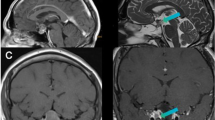

Patient NA, a 46-year-old man. (a–b) Preoperative: Intrasellar and suprasellar hormonally inactive pituitary adenoma, with compression of the optic chiasma. Chiasma syndrome. (c–d) Intraoperative-1: small tumour remnant in the fold of the diaphragm, anterior to the pituitary stalk. (e–f) Intraoperative-2: Complete selective adenomectomy. Normalization of the chiasma syndrome and of the adrenal function. Descent and preservation of the pituitary gland located in the left and middle part of the sella. (g-h) Postoperative 6-month control: Total tumor removal with preservation of the pituitary gland in the middle lateral left position

High-resolution T2-weighted turbo-spin echo sequences in coronal and sagittal views compared with schematic drawings of the typical suprasellar localization of remnant tumor. One of seven cases where the diaphragm did not descend totally while fixed to the pituitary stalk, and a small remnant tumor is exactly localized in the fold of the diaphragm and to the pituitary stalk

Schematic drawing of the typical localization oftumor remnants in transsphenoidal pituitary adenoma surgery. (a) Laterally, close to the medial wall of cavernous sinus (coronal view); (b–d) suprasellar, in the fold of the diaphragm and close attachment to the pituitary stalk (coronal and sagittal views); (c) anteriorly, under descending folds of the diaphragm sellae and posteriorly (sagittal view) as well

In the Target TR group, we observed 23 patients with suspicious tumor remnants: located lateral, close to the medial wall of the cavernous sinus (n = 3), suprasellar, close attachment to the pituitary stalk (n = 7), anteriorly, under descending folds of the diaphragm sellae (n = 7) and also posteriorly (n = 6) (Figs. 7, 8, 9 and 10). In one case, no tumor remnant was found during the “second inspection”, but only blood that was therefore valuated as artifact.

The reason for leaving typical tumor remnants could be that the surgeon tried to avoid anterior CSF leaks, lateral bleeding from the cavernous sinus, and posteriorly did not take time for an adequate drilling of the sella floor into the clivus. In large extended intrasellar and suprasellar adenomas, a typical small tumor remnant is localized in the folds of the descending diaphragm sella and hidden to the surgeon’s eye (Fig. 11).